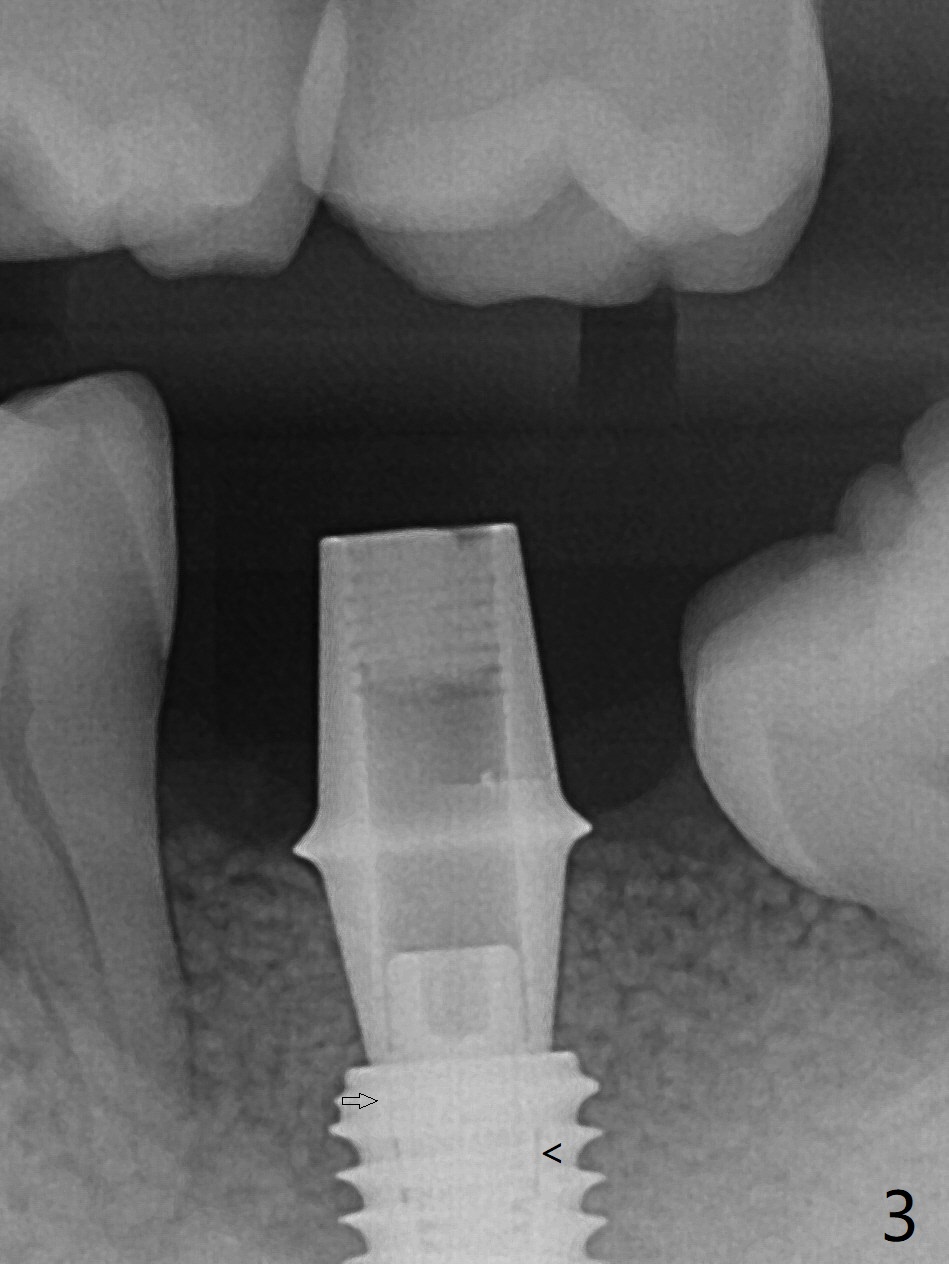

植骨成功必须有两个成分,软硬组织,牙龈提供血运和口袋,而硬组织防止骨粉塌陷。例如即刻植体和基台是可靠,免费(与钛网而言)硬性支撑,今天添加另外一个天然硬性支撑,那就是预后不是很好邻牙。40岁男左下7严重骨质吸收,颊侧,舌侧骨板缺失,骨粉(红色圆圈)将放置6远中,让它发挥余热。8暂时保留,这样7导板稳定些,植入更准确(图一),之后拔除8。结果术中改变计划,得寸进尺,也想保留8,理由骨粉更稳定(图二:*),尤其是远中。6,8牙根面做了刮治。为了证实基台完全就位,又拍摄一张咬翼片(图三),这时植体螺纹清晰。植体与基台之间有两个重要接触部分,第一,图三空箭头,两者必须完全融合(必须没有间隙),理论上可以形成冷焊接(cold welding);第二,短箭头,公母六角形(hex)相接,之间有间隙。如果初步稳定性低,选择愈合基台,与植体交接也必须有X光片验证,两者之间不应该有间隙。如果有间隙,愈合过程,愈合基台很可能脱落,造成病人不安,增加我们工作量,破坏临床进展。图三:术后即刻。术后5.5月(图四)骨粉丧失许多,牙冠外面使用牙周敷料或者直接使用树脂敷料,可能会减少骨粉流失。临床上智齿近中好像没有明显倒凹,取模,估计以后食物坎塞不会太严重。术后6月(牙冠粘固,拧紧25Ncm,图五),螺纹没有暴露。